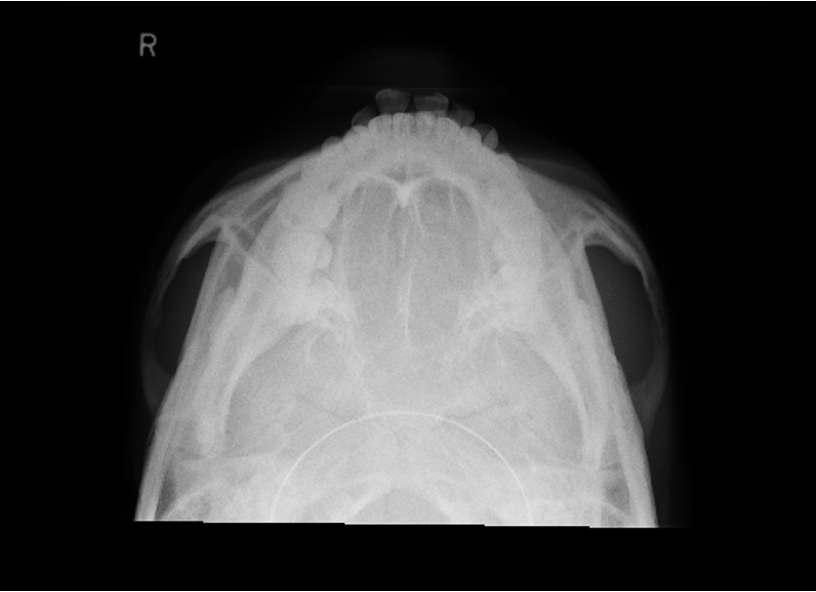

AP axial of skull - Towne method

AP axial skull - Towne method